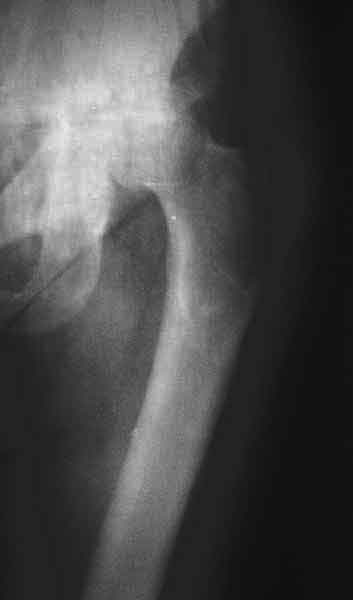

Еще пара фото, ситуация несколько иная, задачи те же, открытое вправление застарелого вывиха в 2002, молодой возраст. Сейчас госпитализирована для эндопротезирования.

Коллеги, обещанный follow-up.

Больного прооперировали на прошлой неделе (цементный протез, цемент с гентамицином). Использовали задне-боковой доступ. В области перелома подвижности практически не было, так что тему сообщения уместно заменить на "неправильно сросшаяся шейка". И в головке, и во впадине

были значительные дегенеративные изменения, так что ни биполяр, ни остеосинтез тут неуместны (хотя это предлагали в ortopod'е). После релиза удлинили ногу на 3 см. Дальше удлинять побоялись из-за

натяжения седалищного нерва, хотя в принципе можно было бы еще 15-20 мм нарастить. По послеоперационной рентгенограмме анатомическое укорочение порядка 15 мм. Клинически при ходьбе - 4 см, но это за счет перекоса таза.

The patient underwent cemented THR on last week. Postero-lateral approach was used. There was only minimal motion at the fracture site and we had to cut the femoral head with oscillating saw. The femoral head was deformed with it's cartilage completely absent in some areas.

Acetabulum showed gross degenerative changes, especially in superior rim. So I think it was right choice not to do ORIF in this case. After some soft tissue release we've lengthened the leg up to 3 cm. Further lengthening was possible but we stopped at that moment due to tension of n. ischiadicus. Now patient walks with crutches. Leg length discrepancy is about 4 cm due to pelvic tilt (discrepancy on post-op x-ray is 15 mm).